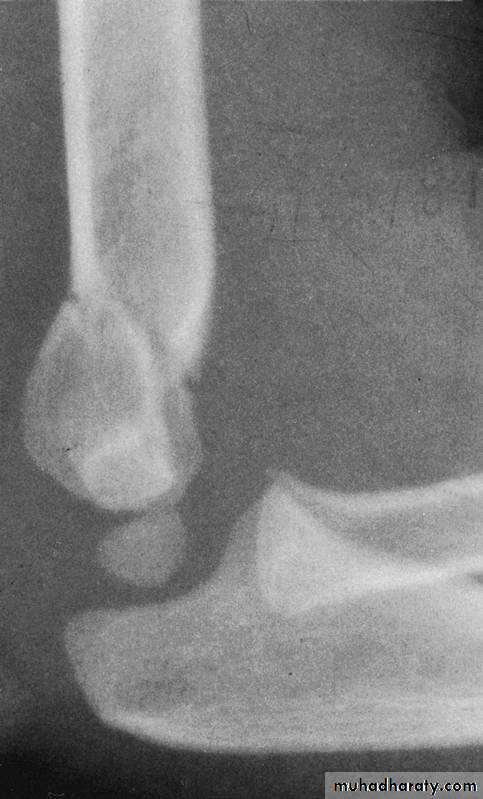

fractures?How are Type III extension supracondylar

fractures sub-classified?Yes

Posteromedial vs. Posterolateral

• Nerve, Vessel Injured

• Surgical Approach

• Rate of Complications

What type has a greater

potential for complications?

The rate of complications is greater with the posterolateral fractures.

What is the major concern

with the posteromedial fractures ?The radial nerve

is more vulnerableto injury.